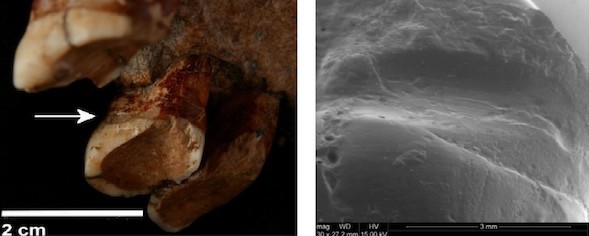

fósil en que se ha observado esta patología fue cedido para su estudio en la UAB, junto con otros restos fósiles del yacimiento de Cova Foradà (Valencia), y posteriormente trasladado al IPHES para el estudio dental. Su cronología no está clara, pero se puede asegurar que es un neandertal asociado a industria lítica musterienses, es decir, de hace aproximadamente entre 150.000 y 50.000 años", informa el IPHES.

La investigación evidenció que los

restos maxilares presentaban porosidad, "un rasgo característico de deterioro por enfermedad periodontal, y pérdida de hueso en los alvéolos (donde están insertados los dientes), con una reducción de la masa ósea de entre cuatro y ocho milímetros, de modo que las raíces de los dientes, normalmente en el interior de los alvéolos, quedaban desprotegidas".

El estudio ha concluido también que el neandertal "no tenía

caries ni había sufrido abscesos, aunque los dientes conservados presentaban un gran desgaste, fruto de una dieta abrasiva, basada en alimentos duros y fibrosos".